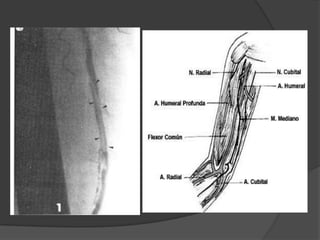

LESIONES ARTERIALES

 Aneurismas

 Estenosis

 Trombosis

 Embolias

 Malformaciones

 Fístulas arteriovenosas